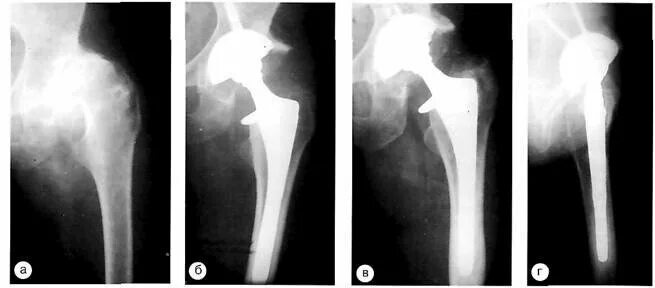

Контрактура после эндопротезирования